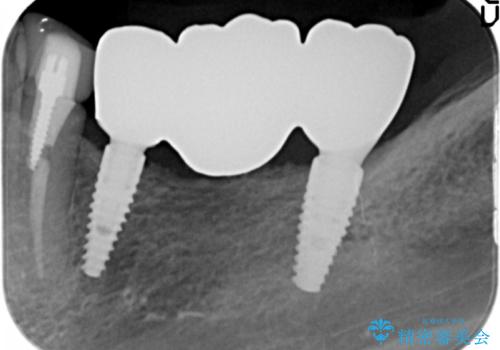

- 90万円(ストローマンインプラント×2・チタンカスタムアバットメント×2・ジルコニアクラウン×3)費用は治療当時の料金となります

インプラントを用いることで、たくさん失ってしまった奥歯を入れ歯よりもしっかりと噛む状態へと回復することができます。